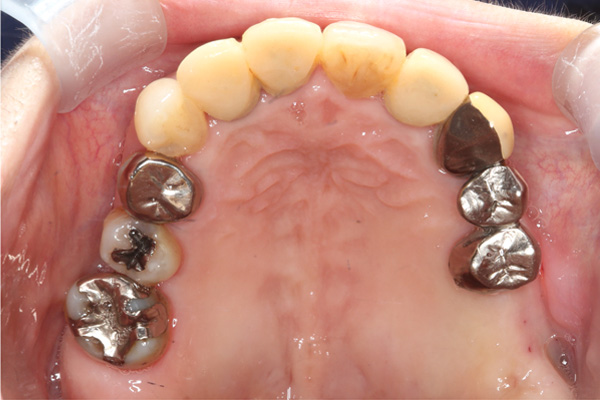

| 年代・性別 | 50代 男性 |

|---|---|

| 主訴 | 右上下の歯が痛い |

| 治療期間 | 約12ヶ月 |

| 費用 | 2,500,000円 |

| 治療内容 | インプラント、骨造成、結合組織移植、セラミック修復 |

| 治療に伴うリスク | インプラント周囲炎 セラミックの破折、脱離 |

*キャンセルポリシーをご一読のうえご予約ください